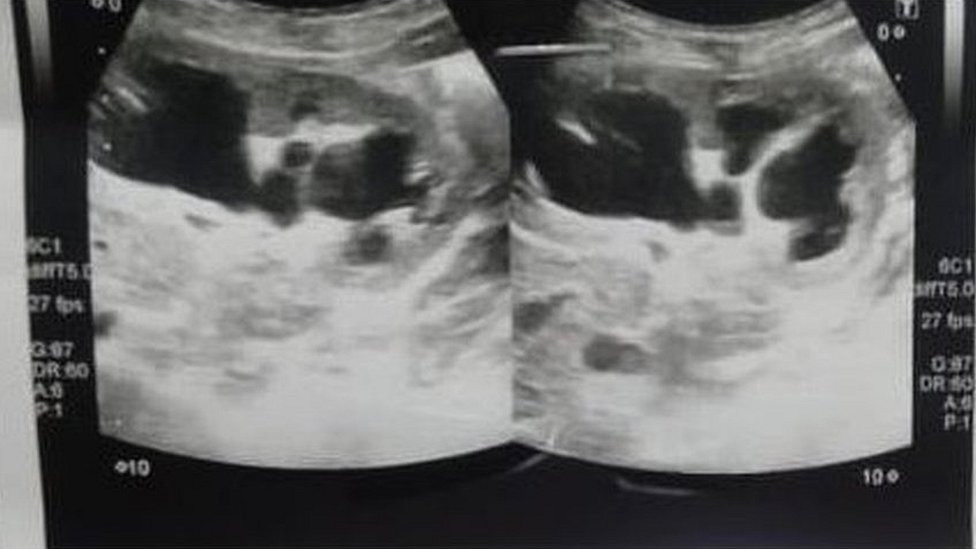

Photo: Sheikh Zayed Medical College

"I did an ultrasound and diagnosed some kind of cyst in the abdomen.